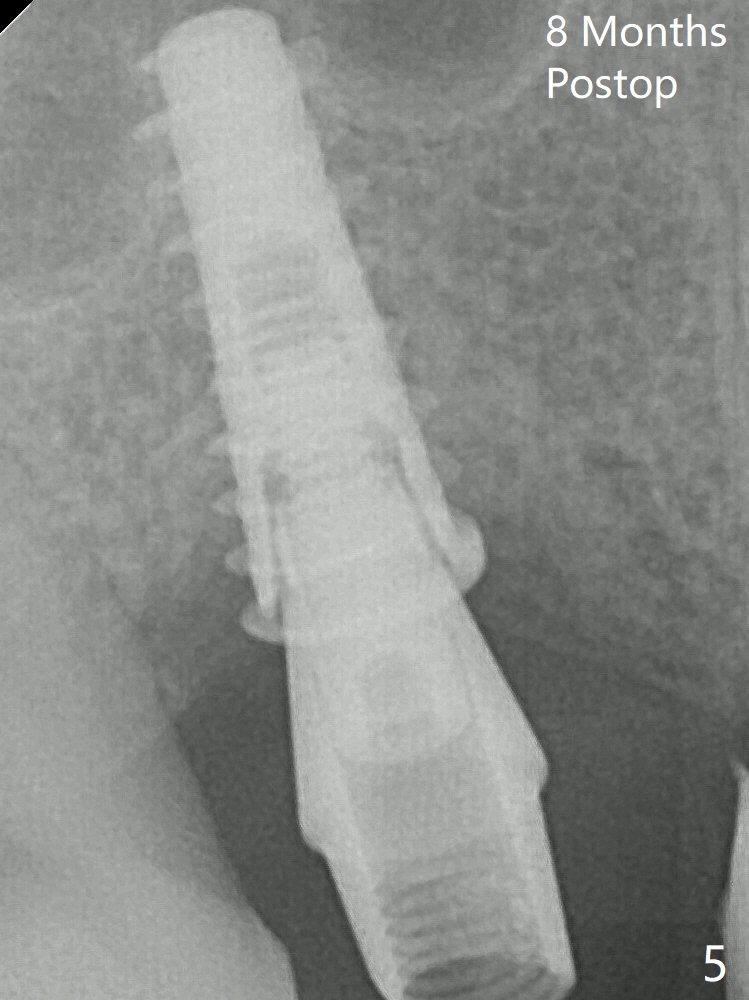

Following the last drill (3.8 mm) for 11 mm, a 4.5x11 mm dummy implant is placed 2 mm subgingival (Fig.2; *: space of the palatal socket). In fact the sinus lift is done by the implant, since the bone plug after Magic Drill is present in the apical portion of the osteotomy when the last drill is finished prior to implant placement. After the dummy implant is removed, the definitive one (the same size) is placed with >50 Ncm, followed by placement of a 4.5x4(3) mm abutment and VeraGraft mixed with autogenous one (Fig.3 *). VeraGraft granules are finer than Vanilla one (.25-1 mm vs. .5-1 mm). There is mild crestal bone loss nearly 8 months postop (Fig.5). An angled abutment (5x15 degree, 3 mm cuff) is used before impression.